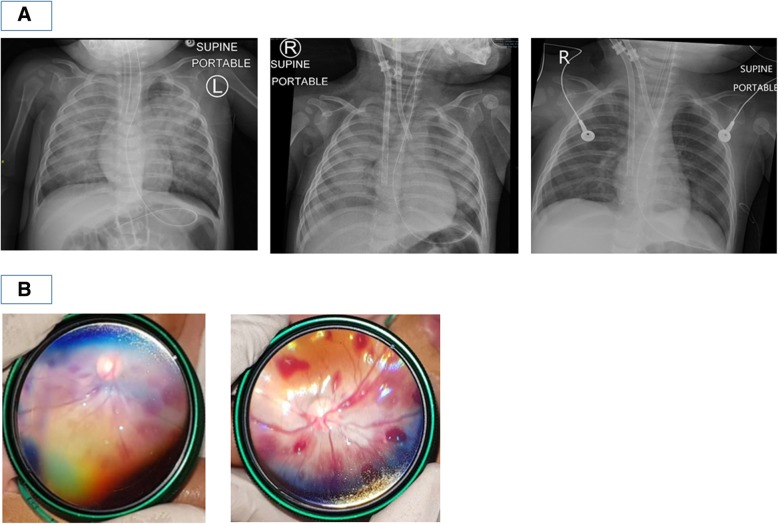

Fig. 2.

a Serial Chest X-rays done showing rapid reversal of pulmonary oedema: leftmost image: done in Children’s Emergency after change of endotracheal tube showing radiographic findings of pulmonary oedema; middle image: done immediately after ECMO cannulation; rightmost image: done the following day, less than 24 h after initiating ECMO. b Slit-lamp examination showing extensive acute bilateral intra-retinal haemorrhages; left image: left retina; right image: right retina

On transfer to the PICU, he continued to have persistent desaturation (SpO2 70–80%) despite adequate ventilation of the patient. Chest X-ray showed bilateral pulmonary airspace shadowing and infiltrates suggesting pulmonary oedema (Fig. 2a). Oxygenation index ranged from 22 to 37.8 in the next 6 h. The patient also continued to have brief clinical seizures and was treated with anti-epileptic medication. He also had worsening haemodynamics, necessitating commencement of inotropic support with adrenaline infusion of 0.03 to 0.1mcg/kg/min to maintain adequate blood pressure.

This was a dangerously ill 9-month-old boy who was previously well presenting with several clinical problems – firstly, convulsive status epilepticus as a result of acute severe brain injury for which CT imaging revealed bilateral acute subdural haemorrhages despite not having a known history of trauma; secondly, rapidly deteriorating cardiogenic shock with resultant flash pulmonary oedema resulting in respiratory failure despite being on high ventilatory support, finally requiring ECMO support. Possible differential diagnoses considered for his acute brain injury were that of underlying undiagnosed bleeding diathesis, intracranial vascular malformation, aneurysm or neoplasia, cerebral infections, rare metabolic disorders such as glutaric aciduria, and lastly non-accidental injury (NAI). His initial coagulation profile and full blood count were both normal, and had no previous or family history suggestive of an underlying bleeding diathesis. His clinical presentation, initial white blood cell count and inflammatory markers did not suggest bacterial sepsis or meningitis, and later viral studies did not suggest viral encephalitis. Magnetic resonance imaging (MRI) brain that was done 2 days after decannulation from ECMO showed bilateral subdural haematomas and mild sulcal subarachnoid haemorrhage. There was diffuse symmetrical white and grey matter signal abnormality and focal areas of parenchymal swelling. These features were suggestive of diffuse brain injury, which may have been a result of hypoxic-ischaemic injury, post-seizure changes, toxic and metabolic derangements or post-trauma changes (Fig. 1b). Magnetic resonance angiography (MRA) brain scan and transcranial doppler (TCD) of major cerebral vessels were both normal. Comprehensive metabolic workup did not reveal any underlying metabolic disorder. Slit-lamp examination of the eyes, which was done on the second day of admission, revealed extensive acute bilateral intra-retinal haemorrhages (Fig. 2b), raising the possibility of shaken baby syndrome. A full skeletal survey did not reveal any other bone fractures. A thorough investigation by the local justice system did not uncover any proof of NAI at home or at his childcare centre.